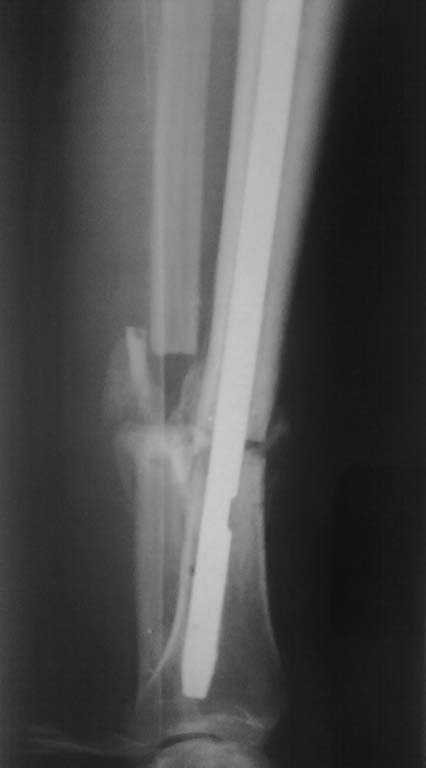

Больной 29 лет, оперирован 3 мес. назад по-поводу открытого перелома обеих костей пр. голени 2 тип по Gustilo (судя по рубцу). Коллеги, подскажите как лучше провести ресинтез: 1. Достаточно ли остеотомии м/берцовой кости или лучше провести частичн. резекцию 2.Проводить ли клиновидную остеотомию б/берцовой кости или возможно исправление оси отклоняющими спицами. P/S: понятно реБИОС, понятно что рассверливание канала. P/P/S: точка входа штифта нетипична - медиально от собств. связки, через бугристоть, проксимальные винты проведены снаружи(!). Спасибо за внимание, с уважением, Дмитрий.

Спасибо большое за советы, но получилось "по-нашенски" - послушал-послушал и сделал по-своему:

1. разобщить отломки м/берцовой кости не удалось - полная консолидация, после остотомии м/берцовой кости в обл. перелома подвижности особой не добились - причина видимо в синостозировании берцовых костей, произвели резекцию, выбрал 2,5см(однако при исправлении оси дефект оказался больше -этого не учел()

2. Пробовал, после резекции м/берцовой кости макс. приводить дист. отломок под ЭОП-контролем, ось исправлялась не до конца, мешала образовавшаяся(все-таки 3 мес.)мозоль, после клиновидной остеотомии (хотя клин оч. узкий брал 3-4мм.) появилась возможность исправить вальгус

3.Поставил 4 позиционных спицы, а вот реконструктивный штифт взять возможности не было, блокировать в динамике после таких манипуляций было страшновато ( да и все-таки это не псевдоартроз), блокировал в статике, продинамизирую - не поленюсь).

Снимки представляю, считаю получилось приемлемо.